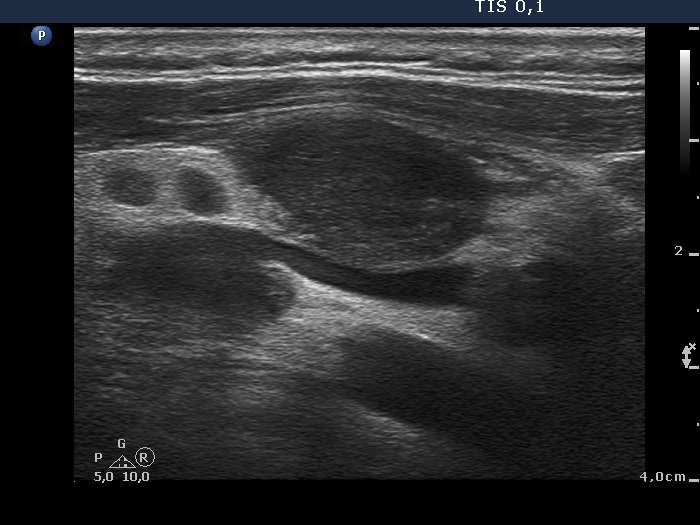

Ultrasonography revealed that the palpable mass contained the enlarged left thyroid composed of a large hypoechogenic nodule with irregular borders and multiple irregular lymph nodes in the left side of the neck.